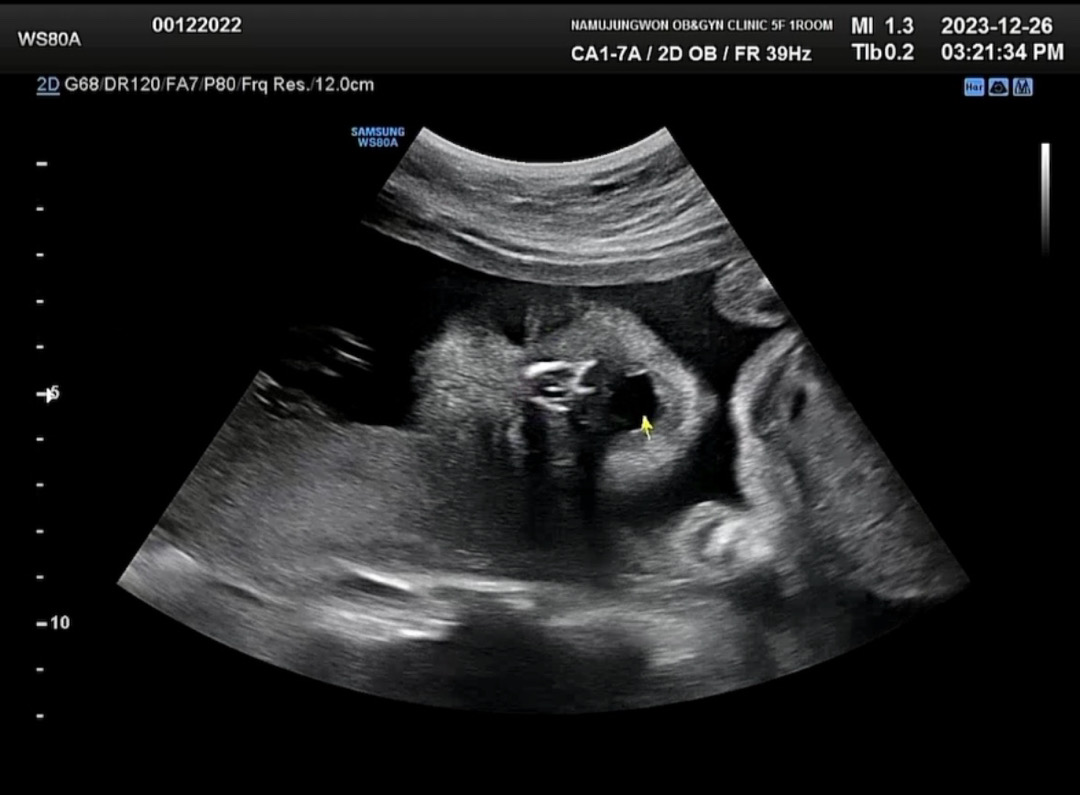

아기 하품하는 사진보세요☺️☺️

영상은 훨씬 리얼한데 사진만 첨부돼서 아쉽네요☺️ 내일은 입체초음파하는데 너무 기대돼요!!

네 ㅎㅎㅎ 주먹쥐고 하품하네요